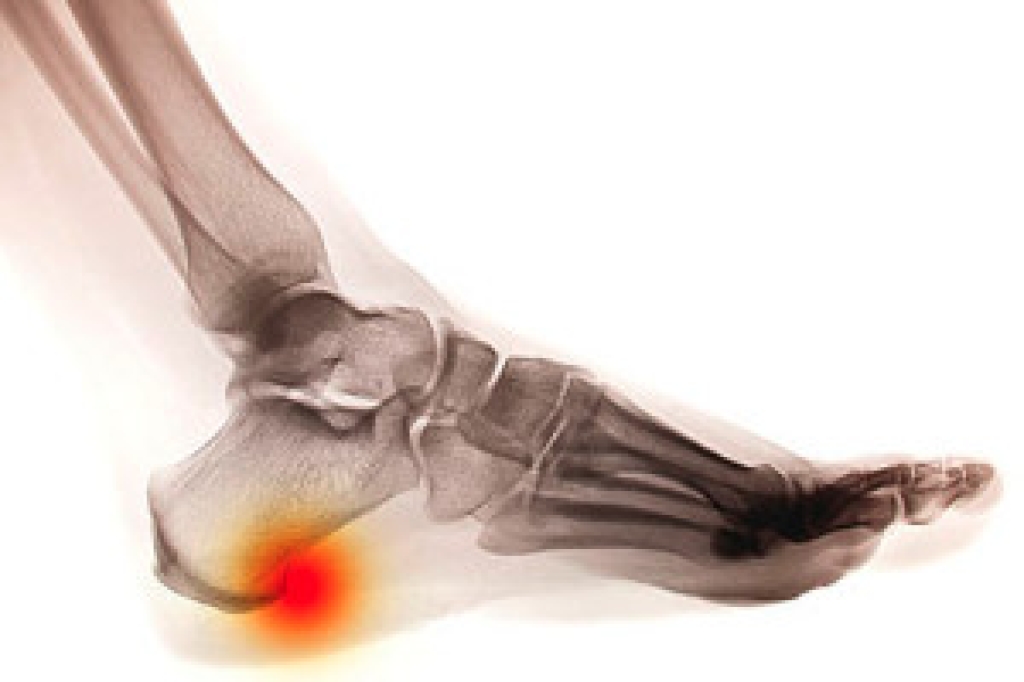

An ankle sprain occurs when the ligaments that support the ankle stretch or tear, usually due to sudden twisting or rolling of the foot. Inversion sprains happen when the foot rolls inward, affecting the outer ligaments, while eversion sprains involve the foot rolling outward, impacting the inner ligaments. Common causes include sports injuries, uneven surfaces, or missteps. Symptoms include pain, swelling, bruising, and limited mobility. Among the risk factors are poor footwear, weak ankle muscles, and previous sprains. A podiatrist can assess the severity of the sprain, provide imaging, if needed, and develop a treatment plan that may include rest, bracing, or specific stretches and exercises. If you experience ankle pain or instability, it is suggested that you consult a podiatrist for expert care and recovery guidance.

In many cases, the RICE method (Rest, Ice, Compression, and Elevate) is used to treat ankle sprains. However, you should see a podiatrist to see which treatment option would work best with your injury. In severe cases, surgery may be required.